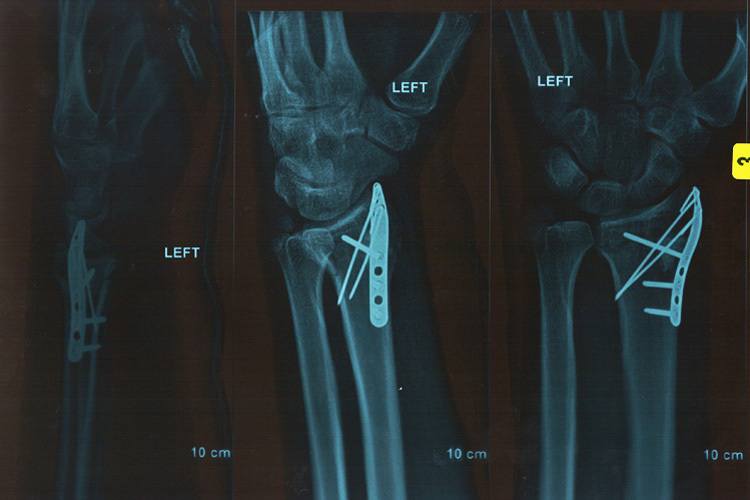

Nach guten Leistungen bei den Wintertestfahrten erwarten der Waliser und das Team ParkinGO MTC Aprilia viel für den Saisonauftakt in Australien. Doch Davies zog sich in einem schnellen Streckenabschnitt in der zweiten Qualifikationssession einen Bruch des linken Handgelenkes und der Elle zu. Inzwischen geht es ihm besser.

"Es geht mir gut, in den paar Wochen habe ich echte Fortschritte gemacht", sagt der Aprilia-Fahrer. "Ich bin ziemlich glücklich und kann nicht mehr verlangen. Mein Handgelenk schmerzt und ist geschwollen, aber es befindet sich in etwa im Heilungs-Zeitplan. Die Ärzte haben mich mit einem abnehmbaren Gips ausgerüstet, dieser wurde vor ein paar Tagen entfernt. Ich kann mein Handgelenk nun wieder bewegen, und die Knochen beginnen zusammenzuwachsen. Mein Daumen scheint noch nicht allzu viel tun zu wollen, aber auch er wird immer besser." Davies erlitt erhebliche Verletzungen, die eine sofortige Behandlung erforderten. Er wurde in Melbourne operiert: "Mein Ellen-Knochen war leicht verschoben und gebrochen, also hatte er sich ein wenig geöffnet. Die Chirurgen renkten ihn wieder ein und befestigten drei Schrauben daran, eine lange und zwei kurze durch den Radius, inklusive einer kleinen Platte. Um richtigen Halt zu gewährleisten, setzten sie dazu noch ein künstliches Knochentransplantat ein. Zwei Drähte wurden eingesetzt, um die Platte an einem anderen Teil des Armes zu halten. An der gebrochenen Elle war keine Arbeit nötig, dieser Bruch kann natürlich heilen." "Der Fortschritt ist gut, ich sehe keinen Grund, warum ich in Imola nicht fahren sollte", bekräftigte Chaz. "Bisher sind wir auf dem richtigen Weg. Ich werde wahrscheinlich nicht zu 100 Prozent fit sein und Schmerzen haben. Aber ich sollte zu 80 oder 90 Prozent fit sein. Dass die Lücken zwischen den Rennen so gross ist, ist für mich wirklich Glück, grosses Glück."